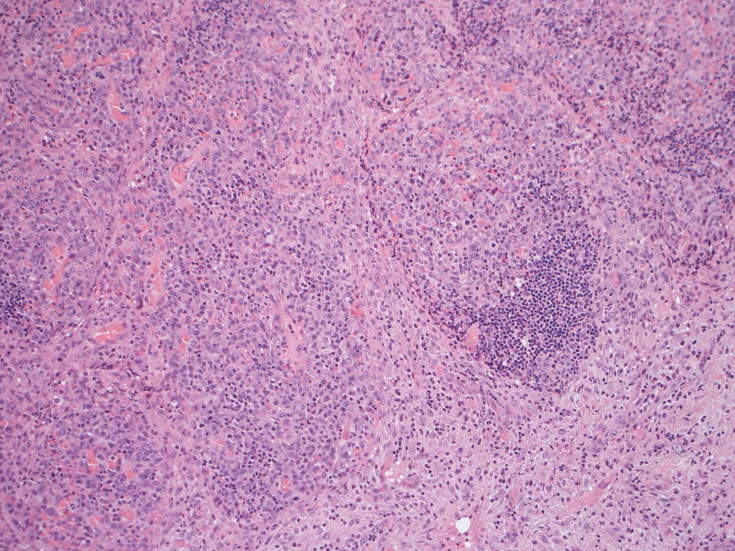

リンパ節, 増殖腫瘍細胞の病理所見

腹膜脂肪組織内から生検されたリンパ節は基本構造を失っている。低倍率のHE所見では異型細胞が不鮮明な結節構造を形成して増殖している。一次リンパ濾胞を腫瘍細胞が置換しているように見える所見がある。

高倍率x400では, 増殖細胞はcentroblastに似て複数の明瞭な核小体をもった淡明な大型類円ないし卵円形核を持っている。核分裂像が多い。この症例では多型はめだたない。典型的な腎臓型のくびれた核を持つ細胞などはない。ALKの形態的variant症例と考えられるが, 化学療法後の再発による影響も否定できない。

リンパ節ルーペ像濾胞内への腫瘍細胞浸潤腫瘍細胞x400